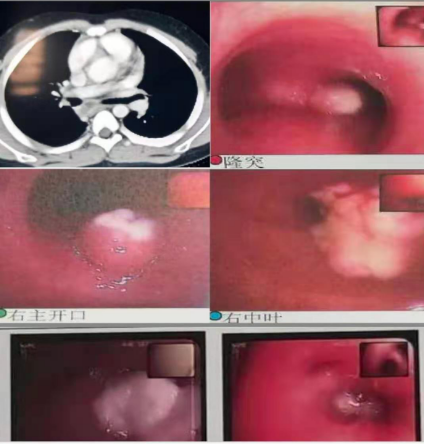

在常见病多发病诊疗基础上,对呼吸系统疑难危重者的诊疗也有独到的优势:重症肺炎的介入治疗(包括盥洗;介入手术取塑性支气管束挽救几近闭塞气管获得再通;利用电切球囊扩张二氧化碳冷冻技术挽救坏死陷闭的气管支气管),支气管异物的取出(包括超过4周的异物造成局部肉芽组织增生、桥联等的诊疗),肺不张的介入治疗可挽救不张的肺叶,降低肺叶切除的风险。支气管扩张症患者定期气道盥洗可改善支扩患儿的生活质量及缺氧情况。已开展气管镜内膜刷检及活检,对EBTB(支气管内膜结核)的诊断,后期可进行局部治疗(包括局部予以异烟肼滴注、钳夹干酪病灶促进病灶恢复等)。随着呼吸专业科研水平提高,对于哮喘支气管哮喘诊断及治疗获得满意的临床疗效,根据炎症介质、哮喘易感基因、哮喘个体化给药基因检测指导临床精准用药、肺功能评估一系列方法的选择,提高了哮喘的诊疗水平。随着二代测序(全外显)的开展,呼吸系统单基因遗传病(囊性纤维化、PCD等)的诊断率逐渐提高,同时呼吸系统病原学的宏基因检测越来越多的应用于临床,减少及避免的抗生素的不合理应用,做到精准诊断精准治疗。

以下为呼吸专业典型病例分享:

图片5:气管内膜结核及重症支原体肺炎所致气道阻塞、塑性支气管束